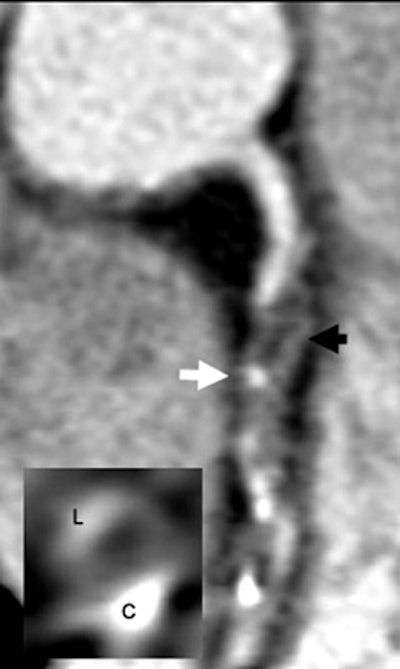

| Plaque type 3 (mixed, predominantly noncalcifying) in 64-year-old man in whom non-ST-segment elevation myocardial infarction (NSTEMI)/ACS was recorded 10 days prior to 16-slice MDCT examination. Black arrow denotes hypodense, dark, noncalcifying plaque component. White arrow is pointing at a small calcifying spot. The inlay bottom-left shows a cross-sectional image of the right coronary artery (RCA) at the level of the white arrow. C = calcifying plaque component, L = lumen. Note that hypodense, black noncalcifying plaque is located between C and L. The lesion was graded as 90% stenosis with interventional coronary angiography. |